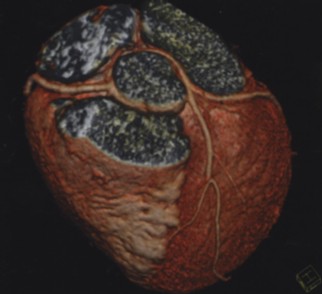

2、心脏冠状动脉成像和心功能评价:由于采用磁悬浮驱动技术与轻量化球管,实现了0.30 秒的旋转速度,2 - 4秒完成对于整个心脏高分辨率扫描,使得冠状动脉检查成功率接近100%,在冠状动脉血管病的变的筛查、冠状动脉支架和搭桥血管评价等方面极具优势。另外利用心脏功能软件,还可以对某些心脏功能指标进行评价。检查更加快捷、舒适、安全,心脏介入术后患者无需住院复查。同时可以为冠心病的筛查及早期诊断提供准确可靠的影像依据。